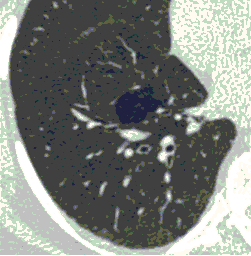

Методы лучевой диагностики применяют для выявления COVID-19 пневмоний, их осложнений, дифференциальной диагностики с другими заболеваниями легких, а также для определения степени выраженности и динамики изменений, оценки эффективности проводимой терапии.

К методам лучевой диагностики патологии ОГК пациентов с предполагаемой/установленной COVID-19 пневмонией относят:

- Компьютерную томографию легких (КТ),

КТ имеет высокую чувствительность в выявлении изменений в легких, характерных для COVID-19. Применение КТ целесообразно для первичной оценки состояния ОГК у пациентов с тяжелыми прогрессирующими формами заболевания, а также для дифференциальной диагностики выявленных изменений и оценки динамики процесса. КТ позволяет выявить характерные изменения в легких у пациентов с COVID-19 еще до появления положительных лабораторных тестов на инфекцию с помощью МАНК. В то же время, КТ выявляет изменения легких у значительного числа пациентов с бессимптомной и легкой формами заболевания, которым не требуется госпитализация. Результаты КТ в этих случаях не влияют на тактику лечения и прогноз заболевания при наличии лабораторного подтверждения COVID-19. Поэтому массовое применение КТ для скрининга асимптомных и легких форм болезни не рекомендуется. При первичном обращении пациента с подозрением на COVID-19 рекомендуется назначать КТ только при наличии клинических и инструментальных признаков дыхательной недостаточности (SpO2 < 95%, ЧДД > 22).

3. Применение лучевых методов у пациентов с симптомами ОРВИ легкой степени тяжести и стабильном состоянии пациента, возможно только по конкретным клиническим показаниям, в том числе при наличии факторов риска, при условии достаточных технических и организационных возможностей. Методом выбора в этом случае является КТ легких по стандартному протоколу без внутривенного контрастирования или РГ при ограниченной доступности КТ. Использование УЗИ в этих случаях нецелесообразно. Применение КТ исследования в сроки ранее 3 - 5 дней с момента появления симптомов заболевания, а также при отсутствии клинических проявлений поражения бронхолегочной системы является нецелесообразным. Выполнение КТ целесообразно при наличии клинических и инструментальных признаков дыхательной недостаточности (SpO2 < 95%, ЧДД > 22), либо при дифференциальной диагностике с другим заболеванием.